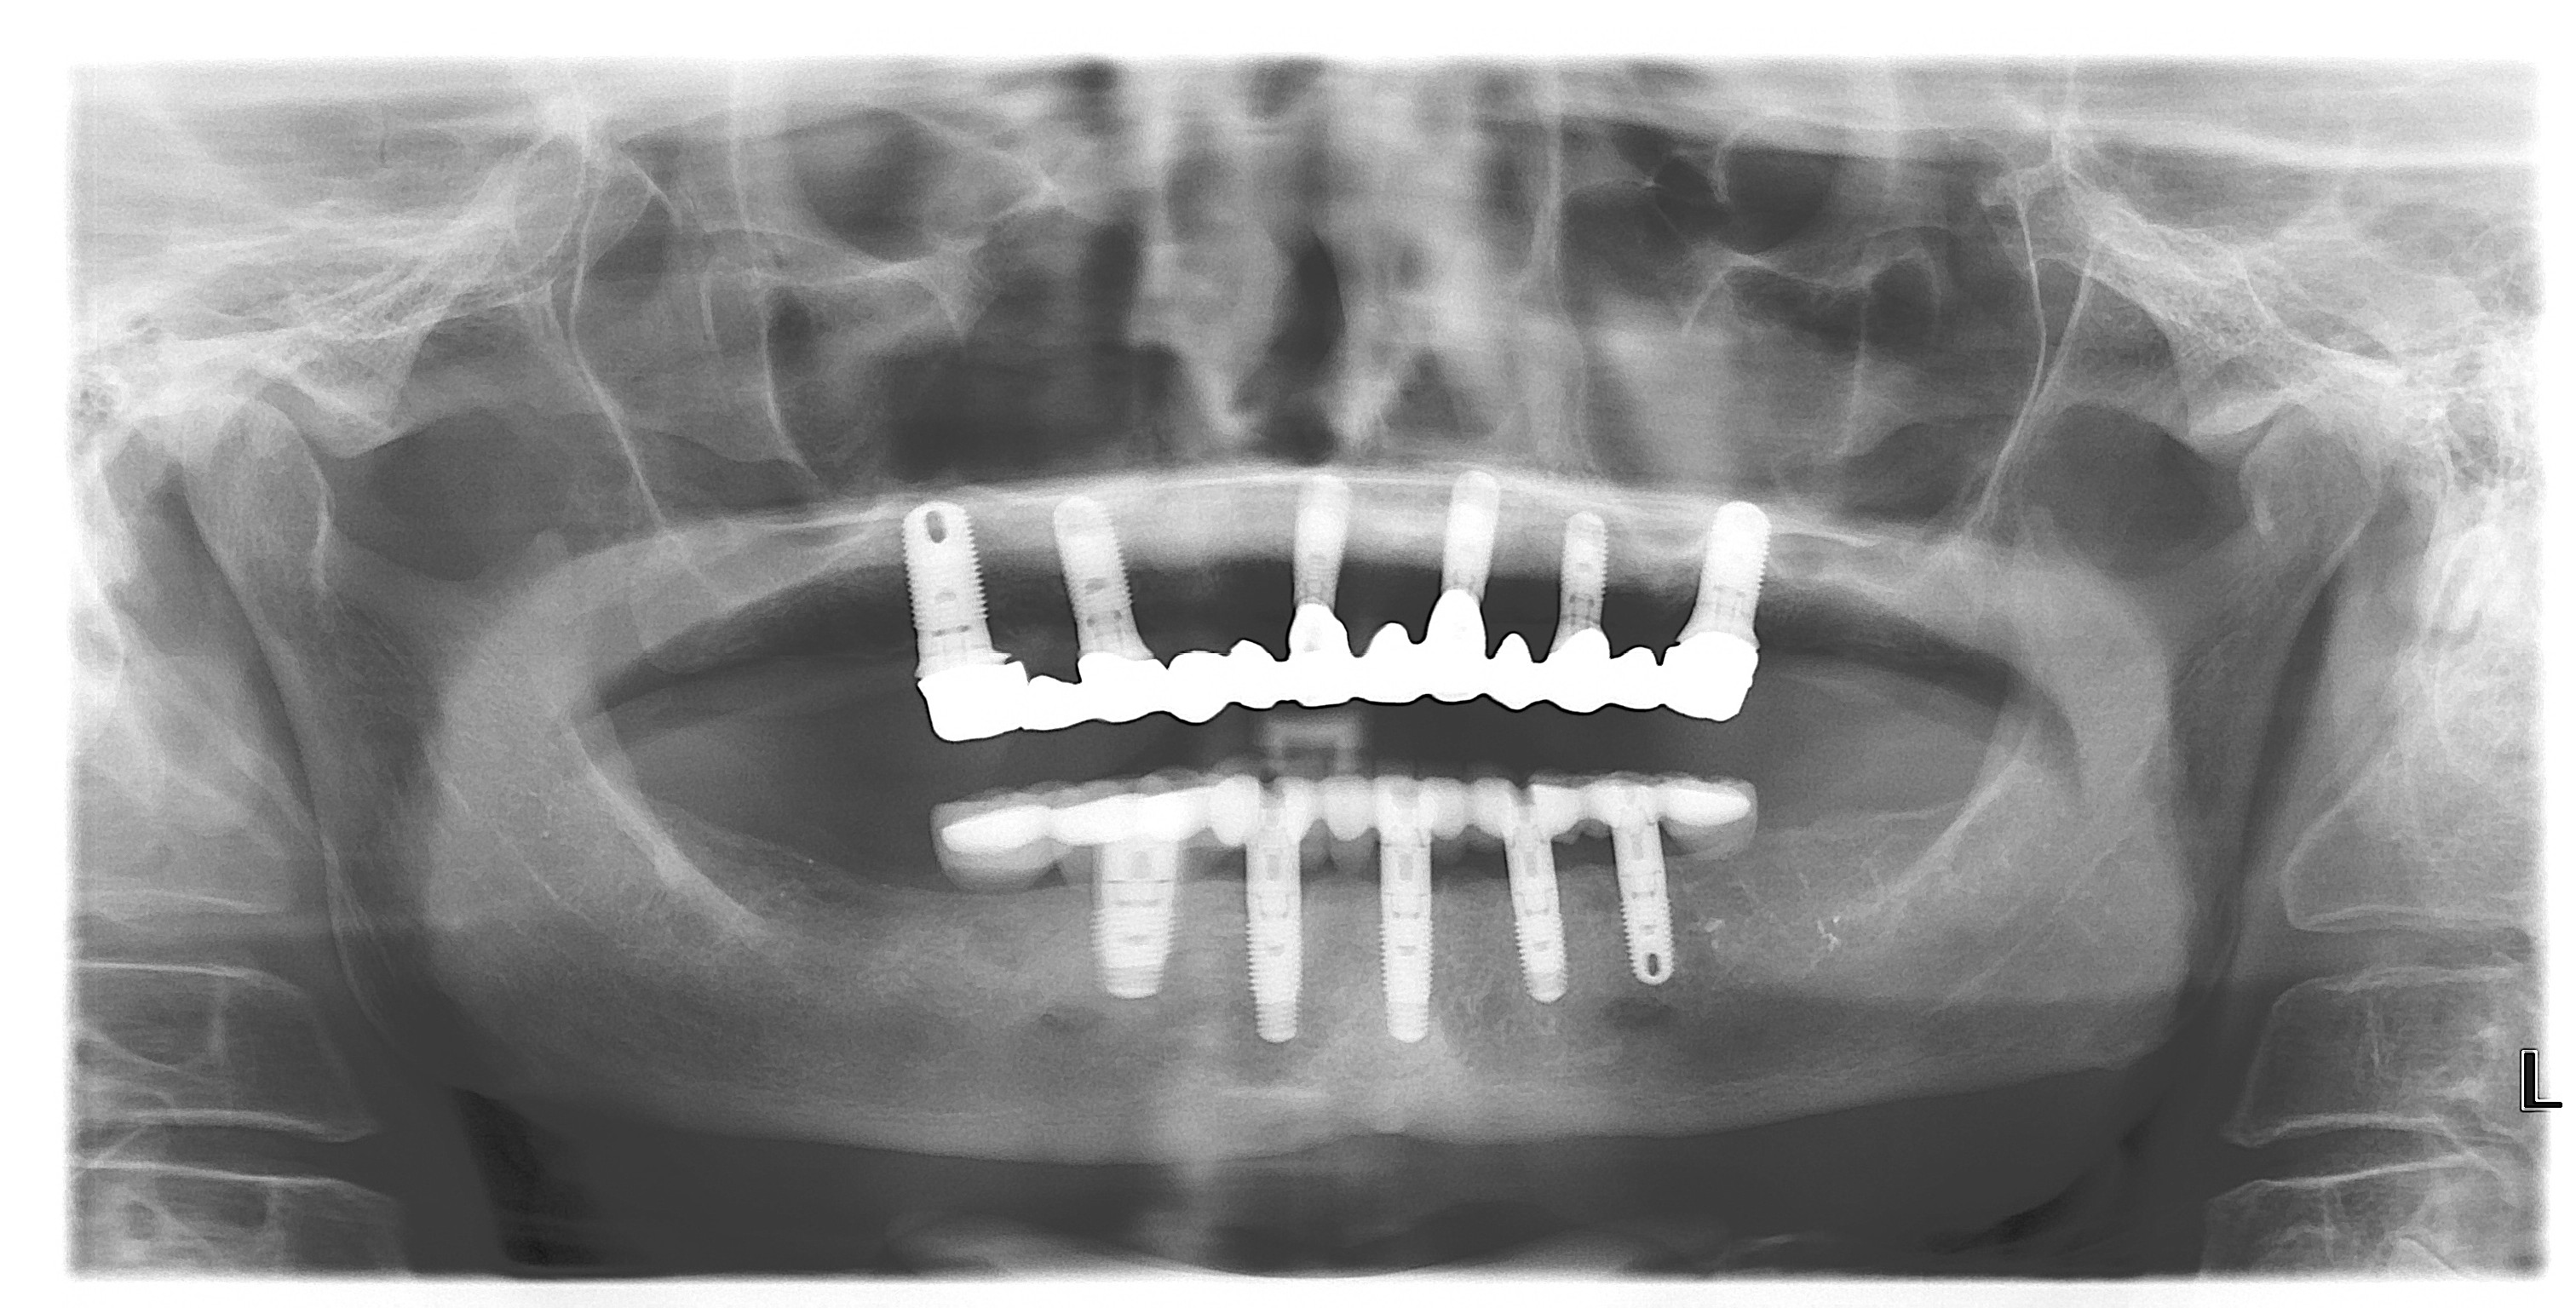

Fig 5. Open margins seen in the radiograph illustration fit issues with large cast-implant frameworks. The milled replacement displayed an intimate passive fit.

Figure 5